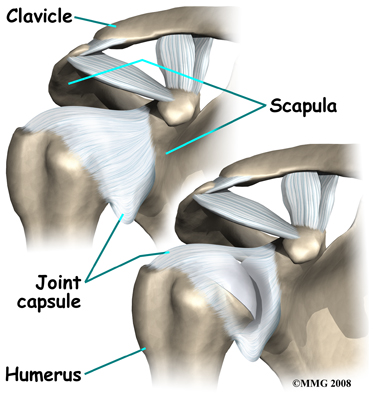

The shoulder is made up of three bones: the scapula (shoulder blade), the humerus (upper arm bone), and the clavicle (collarbone).

The shoulder is made up of three bones: the scapula (shoulder blade), the humerus (upper arm bone), and the clavicle (collarbone).

A watertight sac called the joint capsule surrounds the shoulder joint. The joint capsule holds fluids that lubricate the joint. The walls of the joint capsule are made up of ligaments. Ligaments are connective tissues that attach bones to bones. The joint capsule has a considerable amount of slack (loose tissue), so that the shoulder is unrestricted as it moves through its large range of motion.